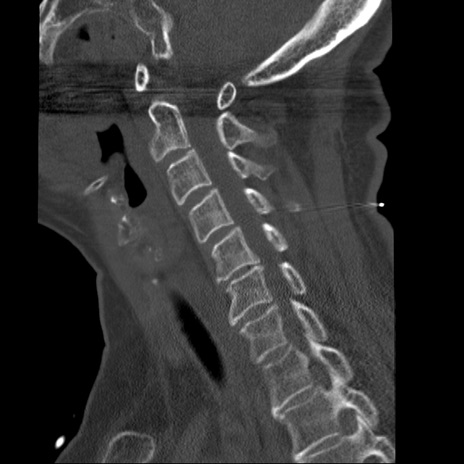

症例50 頚椎CT(矢状断像)

【症例】60歳代女性

【主訴】後頭部〜右後頸部にかけての痛み

【現病歴】本日飲食店でコーヒーを飲んでいたところ、突然後頭部〜右後頸部にかけて痛みが出現し、右上肢の感覚障害を伴ったため救急要請。

【身体所見】脳神経学的に明らかな異常所見を認めず。右上肢に軽度の感覚障害あり。

異常所見と診断は?

頚椎CT